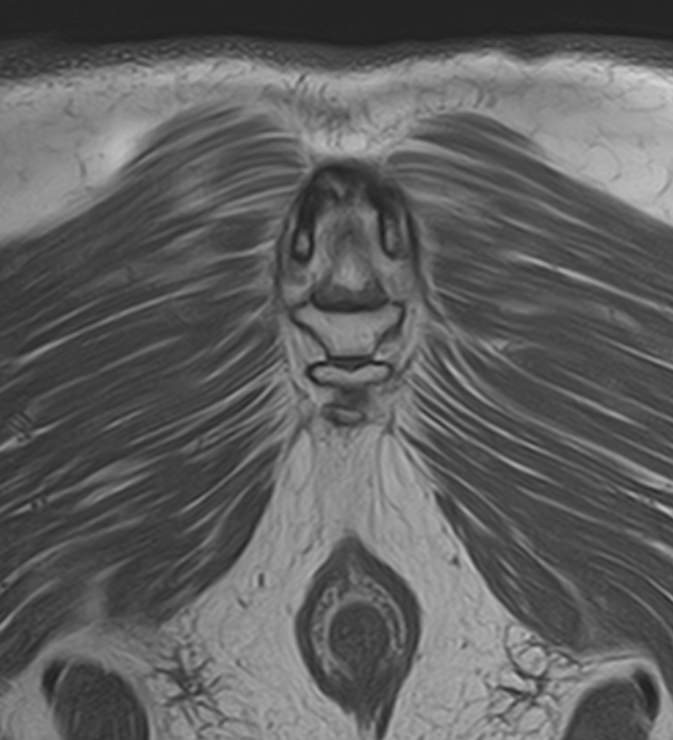

Магнитно-резонансная томография копчика является высокоинформативным методом выявления причин возникновения кокцигодинии. В клинике «Доступная медицина» диагностика осуществляется на новейшем высокопольном томографе закрытого типа TOSHIBA VANTAGE TITAN 1,5 Тесла, обеспечивающем высочайшее качество изображений исследуемой зоны.

Томограф позволяет детально визуализировать как костные структуры копчика, так и окружающие мягкие ткани данной анатомической области, включая мышцы, связки, нервные сплетение, сосуды и прилежащие органы малого таза. МРТ копчика дает возможность диагностировать патологические процессы в самом копчике и выявить их взаимосвязь с патологией окружающих структур.